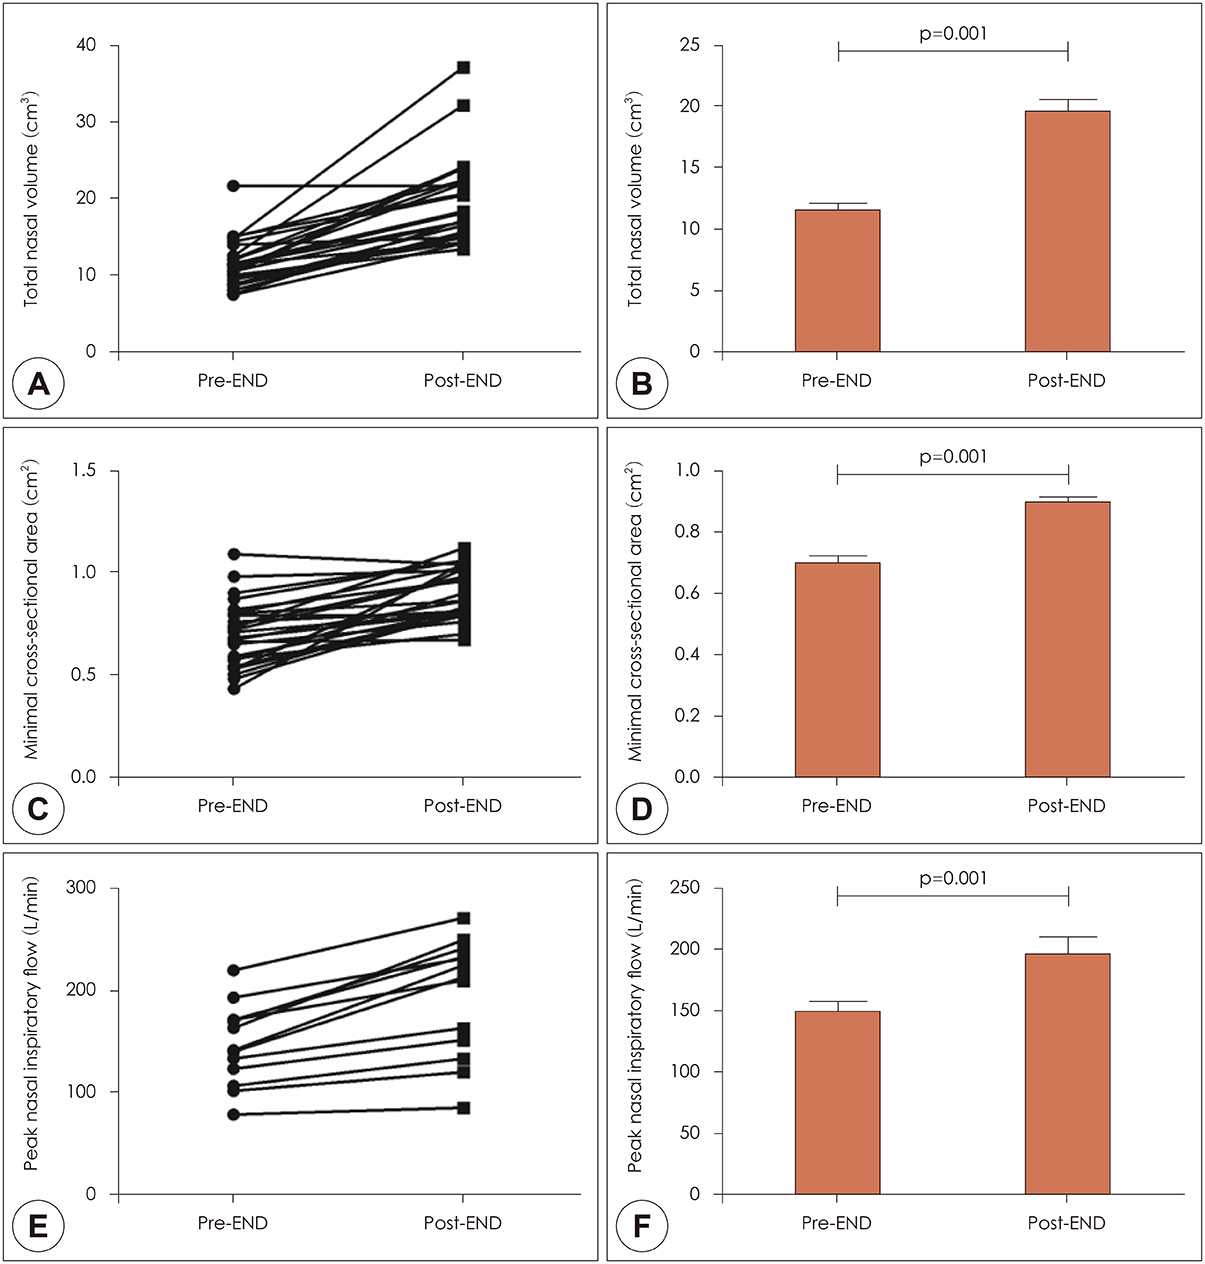

In 13 patients with OSA, changes of total nasal volume (TNV) and minimal cross-sectional area (MCA) before and after END use were evaluated. The change in peak nasal inspiratory flow (PNIF) was also measured. Subjects completed Epworth Sleepiness Scale questionnaire before and 2 weeks after END use. Finally, changes in apnea-hypopnea index (AHI), respiratory distress index (RDI), oxygen desaturation index (ODI), sleep time, sleep position and loudness of snoring (in decibels) were obtained by repetitive portable polysomnography.

RESULTS

After END use, TNV (11.4±3.1 cm3 to 19.4±5.7 cm3) and MCA (0.7±0.2 cm2 to 0.9±0.1 cm2) increased significantly (p=0.001). PNIF also increased significantly after END (147.3±39.5 to 194.6±57.6 liter/min, p=0.001). Among 11 patients undergoing 2-week follow-up, 7 reported improvement in daytime sleepiness. Although AHI, RDI and ODI showed no statistically significant change before and after END (p>0.05), the proportion of subjects sleeping in the supine position increased from 38.0 to 44.5%.